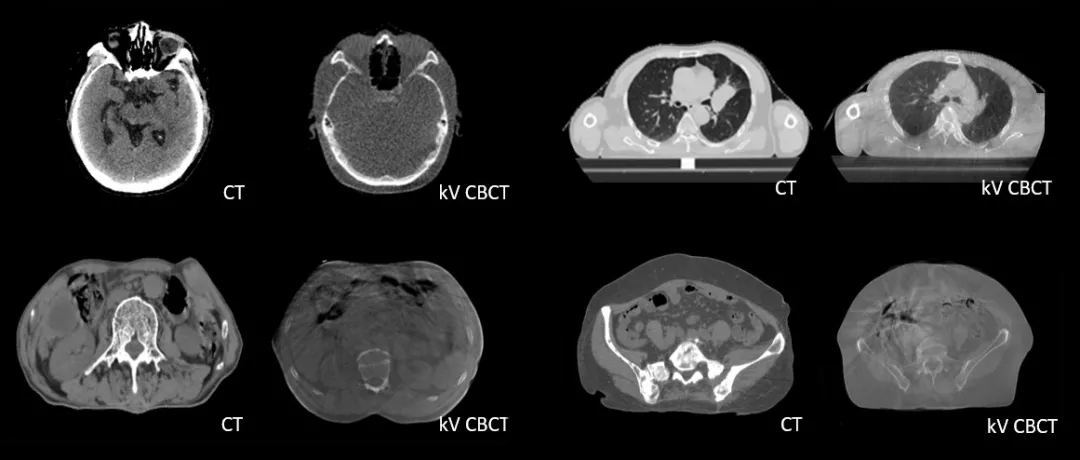

CT-IGRT配準,除骨性標記外,還能以器官、軟組織等作為參考,真正找到配準目標

診斷級 CT對比kV-CBCT影像,更好地顯示器官和軟組織的邊界和細節(jié)